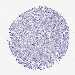

Basal cell and squamous cell cancer

SKIN CANCER - Protein expressioni

A mouse-over function shows sample information and annotation data. Click on an image to view it in a full screen mode. Samples can be filtered based on level of antibody staining by selecting one or several of the following categories: high, medium, low and not detected. The assay and annotation is described here.

Each image is clickable and will lead to virtual microscopy that enables deeper exploration of all samples and also displays staining intensity scores, fraction scores and subcellular localization as well as patient and tissue information for each sample.

Antibody HPA045540

Squamous cell carcinoma, NOS

Squamous cell carcinoma, metastatic, NOS